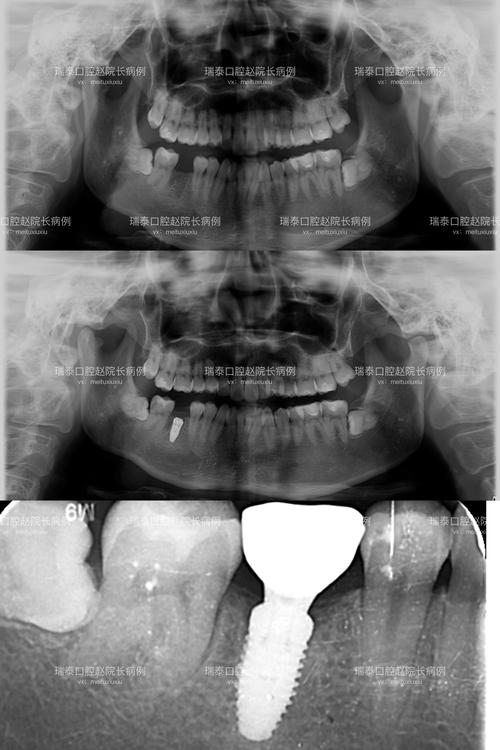

- 现象: 当X射线穿过高密度的金属种植体时,会产生强烈的吸收和散射,导致种植体周围区域的图像信号失真,出现条状、星芒状或模糊的亮区/暗区,这种现象称为金属伪影。

- 影响观察: 特别是观察种植体颈部与牙槽骨交界处以及种植体根尖周围的骨质情况时,伪影会严重干扰。

- 术后评估: 种植手术后,有时需要CT来评估种植体的位置、角度、深度是否理想,以及与重要的解剖结构(如下牙槽神经管、上颌窦)的关系。

- 种植体周围炎的诊断: 当怀疑有种植体周围炎(种植体周围的软硬组织炎症)时,CT可以帮助评估骨吸收的程度和范围,尽管伪影会干扰细节观察,但结合临床检查和其他影像(如根尖片)仍能提供重要信息。

- 其他影像学检查: 对于常规的种植体随访,有时会使用根尖片或全景片,这些检查伪影较小,但显示细节(尤其是三维结构)的能力远不如CT,它们通常用于观察种植体整体位置和骨高度的大致情况,而非精细评估骨结合或微小病变。